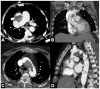

Non-traumatic thoracic aorta emergencies are associated with significant morbidity and mortality. Diseases of the intimomedial layers (aortic dissection and variants) have been grouped under the common term of acute aortic syndrome because they are life-threatening conditions clinically indistinguishable on presentation. Patients with aortic dissection may present with a wide variety of symptoms secondary to the pattern of dissection and end organ malperfusion. Other conditions may be seen in patients with acute symptoms, including ruptured and unstable thoracic aortic aneurysm, iatrogenic or infective pseudoaneurysms, aortic fistula, acute aortic thrombus/occlusive disease, and vasculitis. Imaging plays a pivotal role in the patient's management and care. In the emergency room, chest X-ray is the initial imaging test offering a screening evaluation for alternative common differential diagnoses and a preliminary assessment of the mediastinal dimensions. State-of-the-art multidetector computed tomography angiography (CTA) provides a widely available, rapid, replicable, noninvasive diagnostic imaging with sensitivity approaching 100%. It is an impressive tool in decision-making process with a deep impact on treatment including endovascular or open surgical or conservative treatment. Radiologists must be familiar with the spectrum of these entities to help triage patients appropriately and efficiently. Understanding the imaging findings and proper measurement techniques allow the radiologist to suggest the most appropriate next management step.